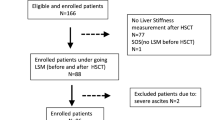

A total of 37 patients were enrolled, but seven did not meet the inclusion criteria and were excluded. Finally, 30 patients were evaluated (Fig. 1).

Flowchart of patient selection 37 patients initially were enrolled. One patient was excluded, because the largest splenic volume (SV) increase on computed tomography (CT) was observed at 2nd month and ultrasonography (US) and shear-wave elastography (SWE) was first performed on the same day as CT, no score of Hokkaido ultrasonography-based scoring system with 10 ultrasonographic parameters (HokUS-10) and liver stiffness measurement (LSM) exist before the largest SV increase to evaluate the ability to predict oxaliplatin-induced sinusoidal obstruction syndrome (SOS). A total of seven patients including the above one patient did not meet the inclusion criteria and were, therefore, excluded from the analysis.